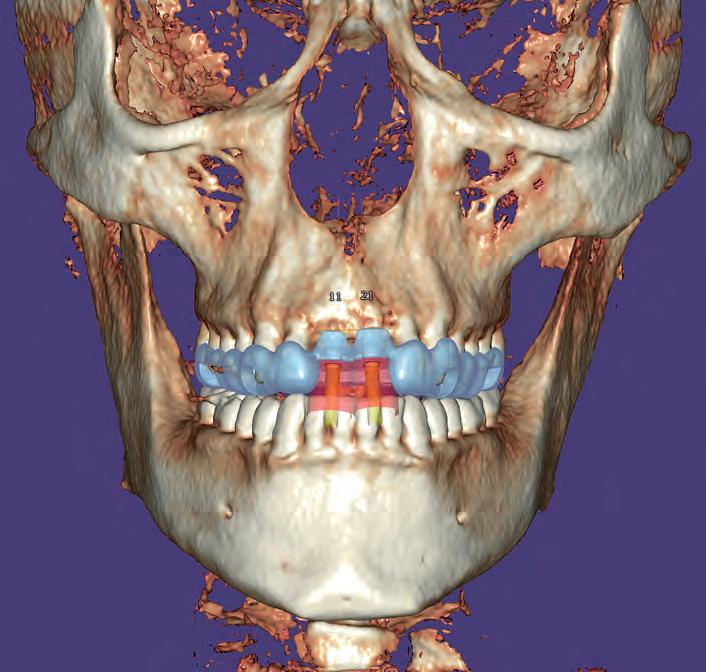

Matt Everatt I EditorPlanned restoration: The patient required a fi xed implant-supported restoration for the upper and lower jaw

Workflow:

- Impression taking and bite registration with existing prostheses; 3D face scans with Face Hunter

-Tooth set-up, digital design in Zirkonzahn.Modifi er to correct occlusion and aesthetics, and fabrication of new prostheses made of Temp Basic resin

-Implant planning and production of surgical guides with Zirkonzahn.Implant-Planner

-Printing the implant models according to the implant planning, with integrated laboratory analogues

-Integration of pins to stabilise the surgical guides the immediate temporaries, ensuring a correct 3D orientation; printing of surgical guides and temporaries

-Implant placement and impression taking after the healing period

-Design and milling of the fi nal restorations in Prettau ® 2 Dispersive ® zirconia

Using CT scans to plan implants is not new and there are several packages on the market. One of the newest on the market and now in its second generation version is exoplan from exocad.

With this product, dental surgeons and dental technicians can accurately correlate intra-oral data, either from a physical or digital impression, and combine it with CBCT

data. Once combined, this package allows for easy and accurate planning of implant placements and the subsequent design and production of surgical guides for the accurate placement of those implants. In addition, the plan can be used in combination with one of exocad's programmes CAD to facilitate immediate loading.

Exoplan is a great addition for a laboratory that already uses exocad for design, as many of the tools used are the same. The surgical guide design is amazingly simple and the fabrication is done with a 3D printer, which many labs have already invested in.